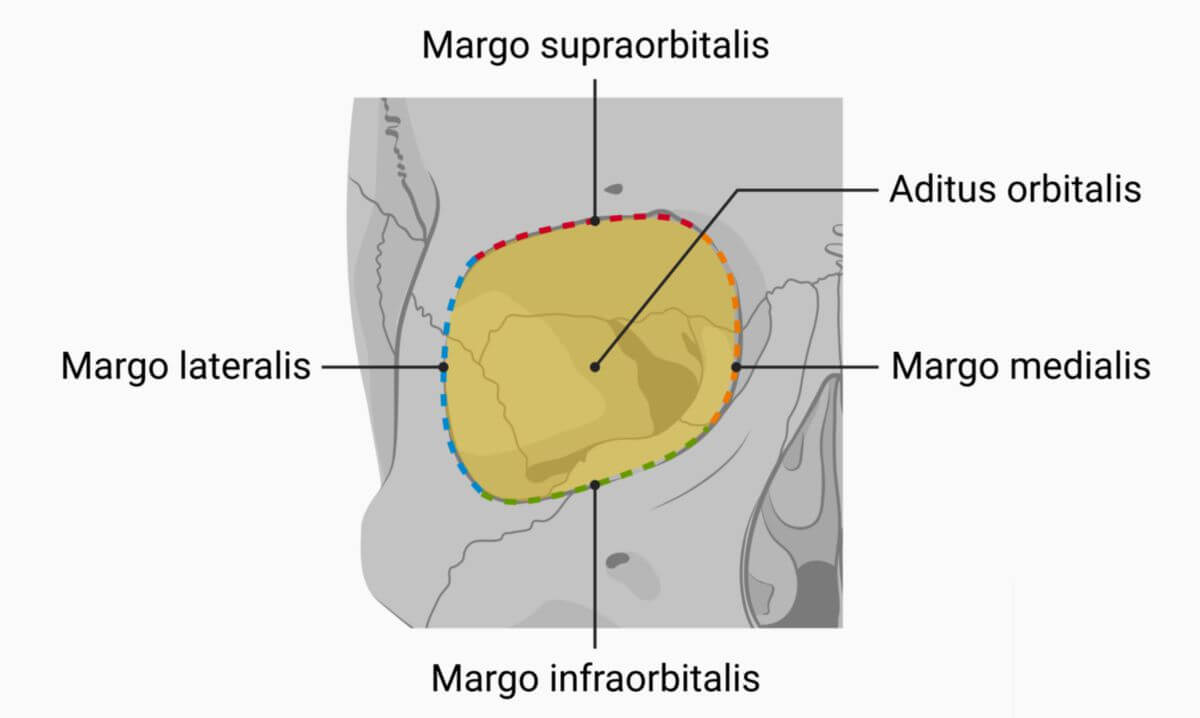

Die Öffnung der Augenhöhle

Die vordere Öffnung, durch die das Auge in der Augenhöhle sichtbar ist, heißt Orbitaöffnung (Aditus orbitalis). Der knöcherne Rand der Orbitaöffnung wird Orbitarand (Margo orbitalis) genannt. (4) Dieser fasst das Auge in der Augenhöhle ein.

Der Orbitalrand wird durch das Stirnbein (gelb), das Jochbein (blau) und den Oberkieferknochen (violett) gebildet. Im Vergleich zu den Orbitalbegrenzungen ist er relativ robust, da er das Auge vor äußeren Einwirkungen schützen muss (2).

! Quelle

TODO: hierzu, die Knochen so einfärben, wie in der Abbildung oben. Vielleicht Namen dran schreiben.

Wie in Abbildung XYZ abgebildet, wird der Orbitarand ebenfalls in oberen (Margo supraorbitalis), unteren (margo infraorbitalis), lateralen (margo lateralis) und medialen (margo medialis) Orbitarand eingeteilt (heißen die wirklich so?).